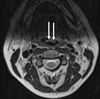

23

Q

A

nasopharynx